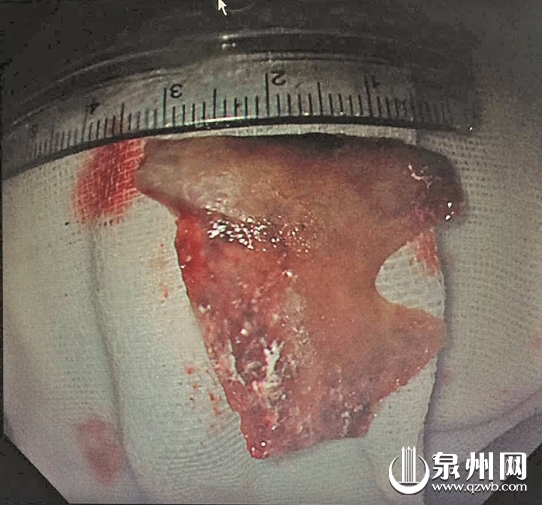

取出的鸭骨头

为确保手术顺利进行,陈相波联系了消化内科、耳鼻喉科、胸外科、麻醉科的同事共同会诊。在众人合力之下,一块3cm×4cm的鸭骨头被顺利取出。